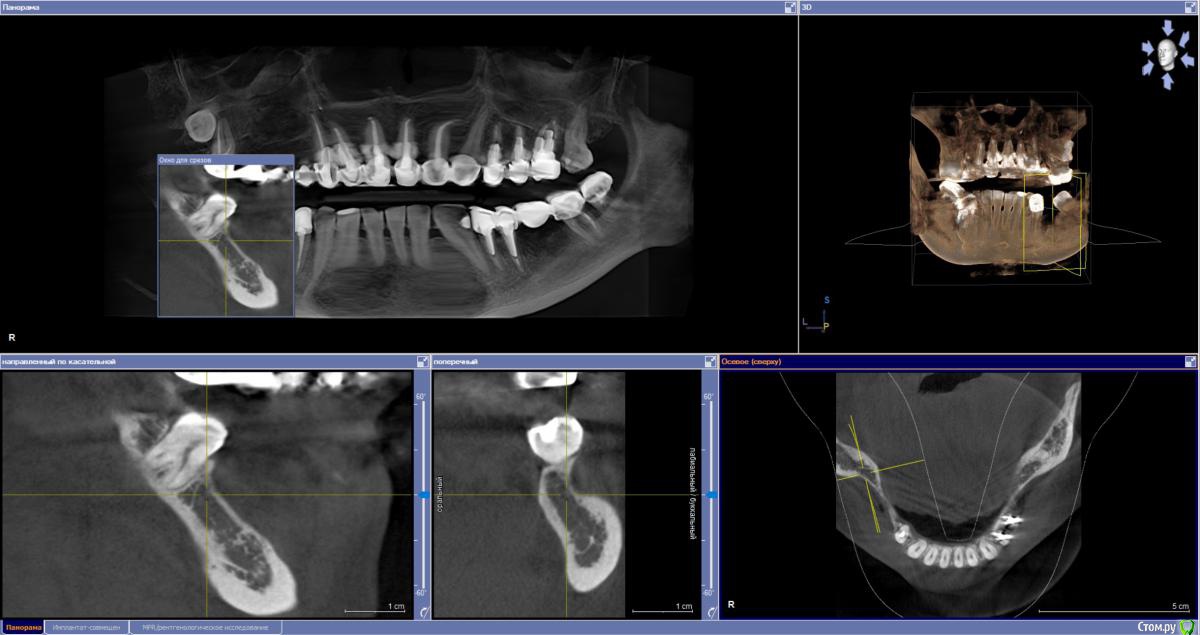

sabik Опубликовано 13 марта, 2019 Поделиться Опубликовано 13 марта, 2019 Хотела б услышать мнение по поводу возможности установки имплантов, ходила в несколько клиник, все говорят разное, общее только то, что на КТ видно, что нет кости вообще, проблема с верхней пазухой,нужна операция лор, еще вопрос можно ли повторить этот мост наверху при отсутствии трех зубов? Не хотят браться за меня нигде Еще беспокоит тупая ноющая боль время от времени, на снимке слева внизу, причину не находят. Подскажите, есть ли зубы на удаление, и какие проблемы видно в общем? Ссылка на комментарий

sabik Опубликовано 14 марта, 2019 Автор Поделиться Опубликовано 14 марта, 2019 Болтается мост сверху, на снимке слева, и беспокоит тупая боль снизу на этой же стороне, жую почти 2 года другой стороной, нужно менять коронки и где возможно установить импланты. Хочу услышать мнение профессионалов по снимку, что можно сделать в моей ситуации. По КТ кости не хватает нигде. Ссылка на комментарий

sabik Опубликовано 23 марта, 2019 Автор Поделиться Опубликовано 23 марта, 2019 Выкладывайте срезы КТПо инструкции с сайта не смогу выложить срезы, нет соответствующей папки (Dicom), но сделала скриншоты (прикреплены к сообщению) проблемных мест в программе. Если не совсем то, скажите, как лучше сделать скриншоты (или видео). Очень нужно мнение специалистов! Ссылка на комментарий

kramer Опубликовано 23 марта, 2019 Поделиться Опубликовано 23 марта, 2019 Источник боли с правой стороны на нижней челюсти пока неясен. Что касается верх право, чтобы ставить имплантаты, надо предварительно делать синус-лифт, до синус-лифта надо приводить пазуху в порядок с помощью ЛОР врача Ссылка на комментарий

sabik Опубликовано 23 марта, 2019 Автор Поделиться Опубликовано 23 марта, 2019 Источник боли с правой стороны на нижней челюсти пока неясен. Что касается верх право, чтобы ставить имплантаты, надо предварительно делать синус-лифт, до синус-лифта надо приводить пазуху в порядок с помощью ЛОР врача Спасибо, что ответили! Возможно ли поставить импланты снизу справа? А слева какая ситуация, есть ли кисты. удалять надо зубы или нет, все говорят разное просто, очень сложно понять кто прав(( Ссылка на комментарий

Nazim_NV86 Опубликовано 23 марта, 2019 Поделиться Опубликовано 23 марта, 2019 Возможно ли поставить импланты снизу справа? Возможно. А слева какая ситуация, есть ли кисты. удалять надо зубы или нетПроблемы есть. Нужно во рту смотреть и томограмму. Вы срезы не те выкладываете. Этот Galileos только с диска читается. Ссылка на комментарий

sabik Опубликовано 2 апреля, 2019 Автор Поделиться Опубликовано 2 апреля, 2019 Предлагают два варианта постановки имплантов справа внизу: первый вариант - поставить 2 импланта вместо 5 и 6 зуба, с подсадкой кости, расщеплением гребня, а второй вариант- 2 импланта вместо 5 и 7 зуба, с подсадкой кости только на 5 зубе, а на место 7-го имплант сразу ровно поставленный, и позже мост . 7 зуб живой, но с наклонном, боль есть тупая, говорят может он один там и нагрузка идет на него, не знаю, из-за этого может болеть он временами или нет, перидонтальная щель расширена чуть тоже. Как считаете, какой вариант имплантации лучше? Ссылка на комментарий